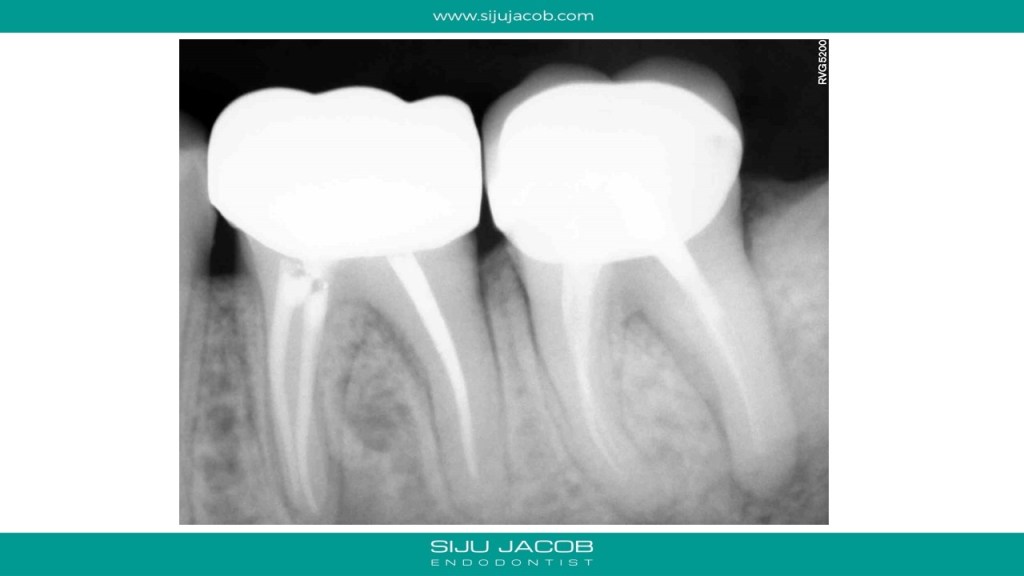

This patient had pain followed by a sinus tract on a previously endo treated and crowned mandibular second molar. The Distal root had a lesion. The Mesial root, although short, didn’t have any lesion. So, I decided to leave the mesials alone. I placed Calcium hydroxide, waited for the sinus to heal and then Obturated.